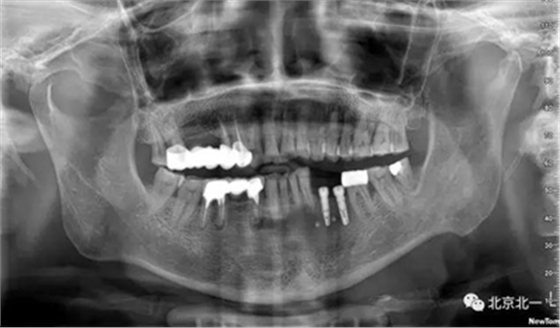

患者術(shù)前片, 最窄骨寬度僅僅3mm,34-35牙位缺失,

CBCT顯示如下圖

如何種植?

采取骨替代品移植后蓋膜,膜釘固定。

手術(shù)后半年觀察, 成骨良好。

總結(jié):水平骨增量主要解決骨粉固定,骨膜穩(wěn)定以及血供, 穩(wěn)定壓倒一切, 血供成就一切。 僅此而已。 這就是水平骨增量的精髓所在。